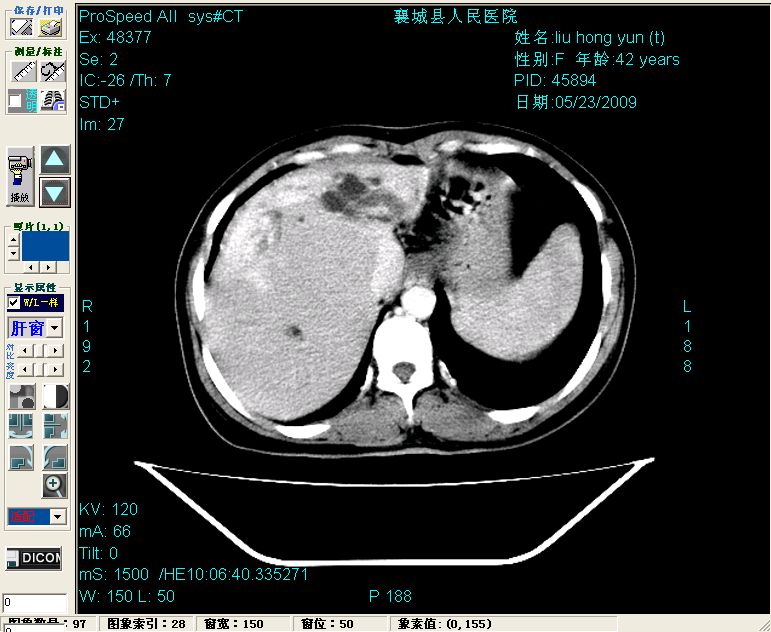

增强:

增强动脉期前述低密度区轻度早其强化,门脉期强化程度显著增高,延期扫描强化程度下降,但仍为相对高密度影

胰头部见结节状高密度影,其前方略可分辨扩强胆部管,平扫到增强始终有,但现在尚难与胃肠造影剂鉴别.